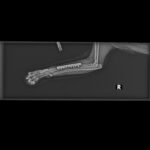

Noch in derselben Nacht kam ich in die Klinik. Mein linkes Auge war durch ein schlimmes Glaukom zerstört – es musste sofort entfernt werden. Das andere Auge ist leider auch krank. Die Linse ist verrutscht, und die Tierärzte sagen, dass auch dieses Auge bald raus muss. Dann bin ich blind. Aber wenigstens schmerzfrei.